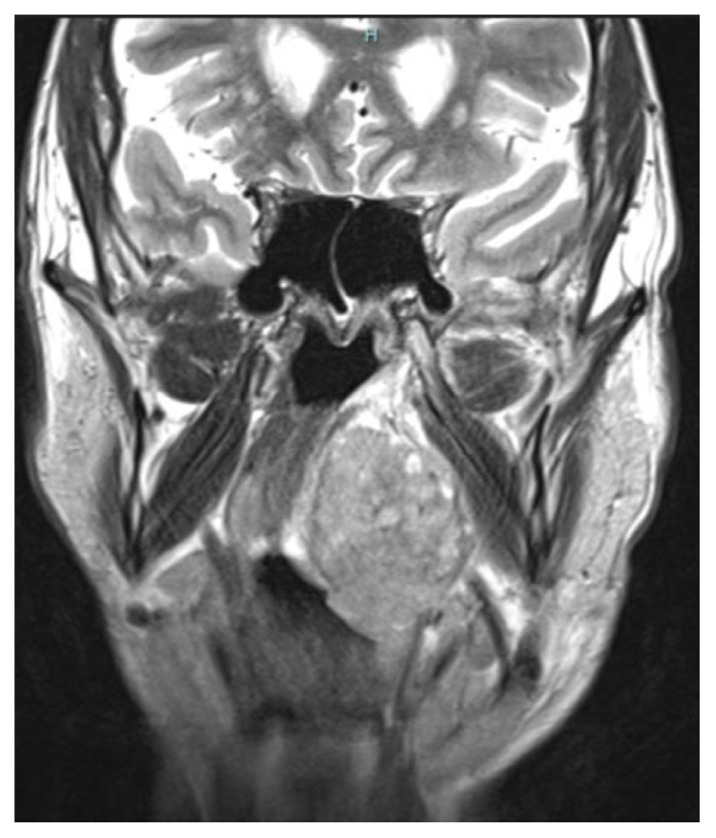

Abstract Image